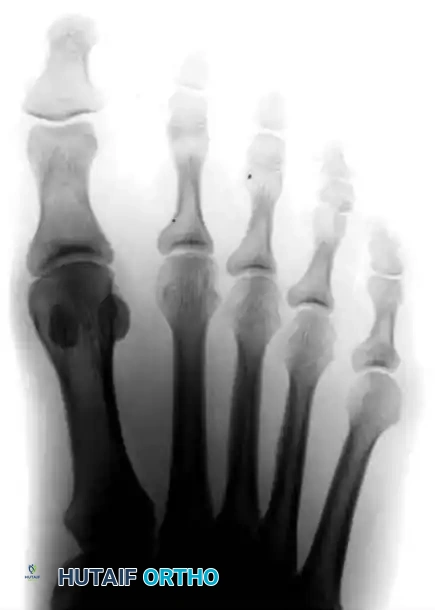

Radiographic Evaluation

Standard weight-bearing anteroposterior (AP), lateral, and oblique radiographs of the foot are mandatory for the accurate assessment of a bunionette deformity. The AP radiograph is utilized to measure several critical angles that dictate surgical decision-making.

Key Radiographic Parameters

- 4-5 Intermetatarsal Angle (IMA): Formed by the intersection of the longitudinal axes of the fourth and fifth metatarsals.

- Normal: Less than 8 degrees.

- Pathologic: Greater than 8 degrees indicates pathological divergence of the fifth ray.

- Fifth Metatarsophalangeal (MTP-5) Angle: Formed by the longitudinal axis of the fifth metatarsal and the longitudinal axis of the proximal phalanx of the fifth toe.

- Pathologic: Usually greater than 14 degrees in symptomatic patients.

FIGURE 83-40 Measurement of metatarsophalangeal-5 and 4-5 intermetatarsal angles for evaluation of bunionette deformity.

- Lateral Deviation Angle (LDA): This angle evaluates the intrinsic bowing of the fifth metatarsal shaft. It is formed by a line bisecting the metatarsal head and neck intersecting with a line drawn parallel to the medial cortex of the proximal fifth metatarsal shaft.

- Normal: Approximately 2.6 degrees.

- Pathologic: Averages 8 degrees in patients with a symptomatic bunionette.

FIGURE 83-42 Measurement of lateral deviation angle in the evaluation of bunionette deformity.

Type III: Widened 4-5 Intermetatarsal Angle

Type III is the most common variant. It is characterized by a divergent fifth metatarsal shaft resulting in an increased 4-5 IMA (greater than 8 degrees). This divergence significantly widens the forefoot (splayfoot).

FIGURE 83-41C Type III, widening of the 4-5 intermetatarsal angle.